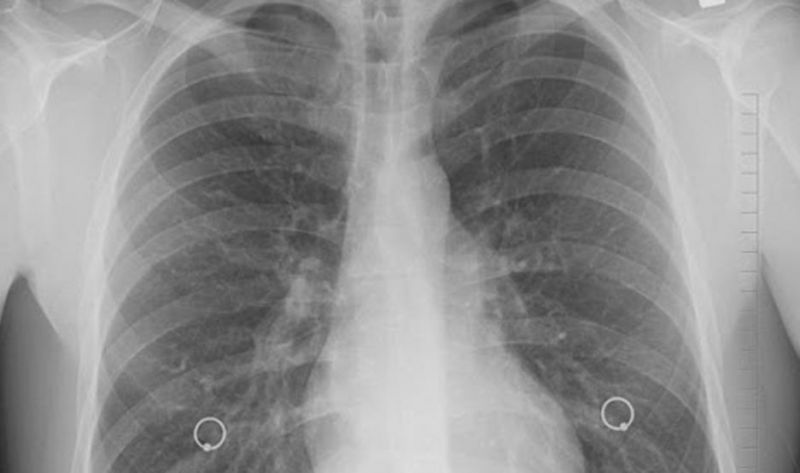

Además, las radiografías de tórax revelaron "opacidades bilaterales de vidrio esmerilado", hallazgos consistentes con el síndrome de dificultad respiratoria aguda (SDRA).